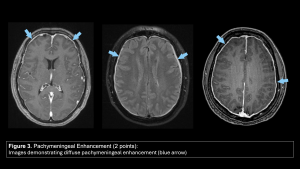

- Pachymeningeal Enhancement (2 points):

- Positive: Smooth, continuous, non-nodular enhancement of the dura mater (sparing the leptomeninges). This is the most common sign, but it can be absent in chronic cases.